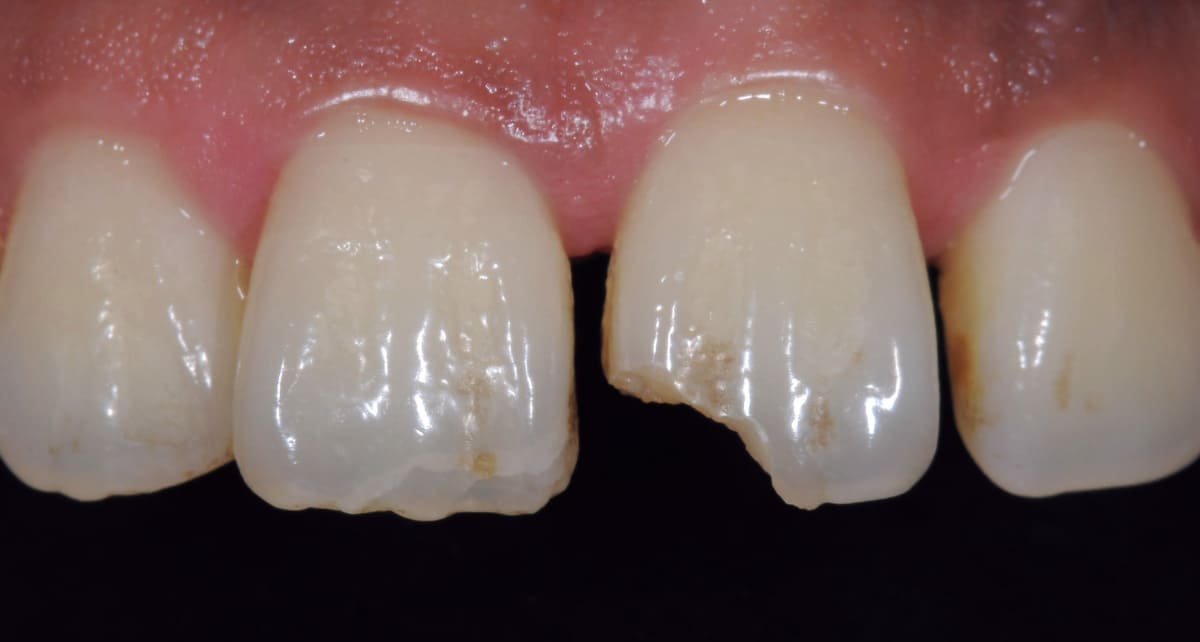

ダイレクトボンディング|ペースト状の材料を歯に盛り付けるだけ。

Before

After

むし歯や前歯の隙間、欠けた歯を修復する治療。セラミックとプラスチックの混合物であるレジンというペースト状の材料を直接歯に盛り付ける。クラウンのように型取りする必要もないので短期間で済み、歯を削る範囲も最小限。

【料金】3万円〜

【治療期間】1日〜2週間程度